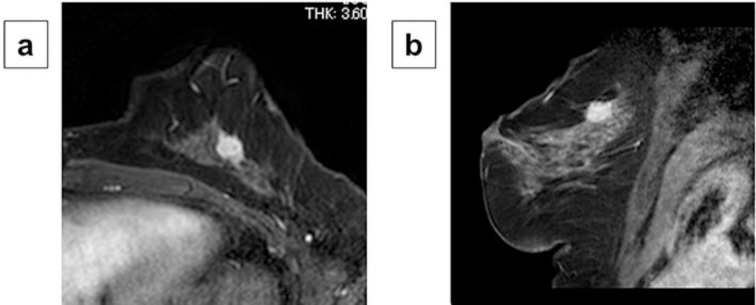

Fig. 2.

Magnetic resonance imaging findings: Contrast-enhanced magnetic resonance imaging (MRI) revealed the primary tumor to be a mass 15 mm in size with spicules, which exhibited early phase enhancement (a: transverse plane) (b: sagittal plane).

A 56-year-old woman with a left breast mass identified by mammographic screening was examined at our institute. She had no prior medical history or family history. During physical examination, palpation revealed an elastic hard mass of approx. 1.5 cm in the upper outer quadrant of the left breast in the vicinity of the areola. Breast ultrasound revealed a sharply marginated, hypoechoic mass 12.7 × 9.4 × 8.7 mm in size in the upper outer quadrant of the left breast (Fig. 1a), and a vacuum-assisted biopsy (VAB) was performed at the mass site. Pathological examination of the VAB specimen by hematoxylin and eosin (H&E) staining revealed atypical cells with a cribriform growth pattern, and mucosal fluid surrounding tumor nests and within tumor ducts (Fig. 1b). The area around the tumor nests and inside of tumor ducts were also positively stained with alcian blue (Fig. 1c). Tumor ducts contained a mixture of areas positive and negative for p63 and CK5/6 expression. Together with these immunohistochemical findings, we reached a pathological diagnosis of ACC. The tumor was ER-negative, PgR-negative, and HER2-negative, with low Ki67 expression. Computed tomography (CT) findings also did not reveal lymph node metastases or distant metastases. Contrast-enhanced magnetic resonance imaging (MRI) revealed the primary tumor to be a mass 15 mm in size with spicules, which exhibited early phase enhancement (Fig. 2a, b). The preoperative diagnosis was stage I (cT1N0M0) triple-negative left breast cancer (ACC). Surgery consisted of breast-conserving surgery and sentinel node biopsy. The excised specimen was a 15.0 × 12.1 × 9.7 mm mass with a greyish white cut surface (Fig. 3a). Pathological examination of the excised specimen by H&E staining revealed a so-called adenoid cystic pattern, with various large and small cribriform mucinous tumor nests around the tumor stroma, and both true and false lumen within the tumor nests (nuclear atypia: score 3, mitotic count: score1, nuclear grade: grade 1, ly0, v0, stump margin positive) (Fig. 3b). Results from immunohistochemical staining were identical to those from a VAB specimen, as they were ER-negative, PgR-negative, and HER2-negative, with low Ki67 expression. No lymph node metastases were found in the sentinel node biopsy specimen. The final diagnosis, given the above findings, was left breast cancer (ACC) pT1N0M0 stage I triple-negative subtype. No systemic adjuvant therapy was performed after surgery due to the low risk of recurrence based on an absence of lymph node metastases and a favorable prognosis for ACC. After 6 months of observation without treatment, there has been no recurrence or metastatic onset.